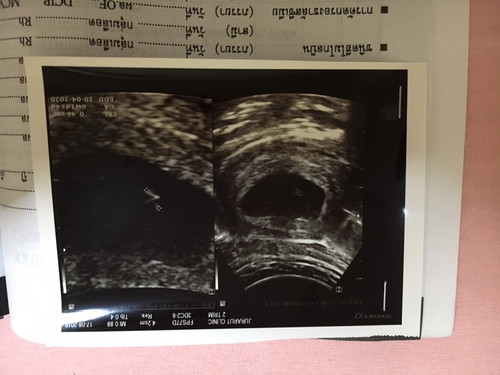

6wแล้ว แต่หมอบอกว่า ลูกตัวเล็กมาเลย กังวนมากเลยค่ะ

6 วีค หลายๆคนยังไม่เจอตัวอ่อนเลยจ้า อายุครรภ์ยังน้อย ตัวอ่อนยังเล็กมากกกกจ้า ไม่ต้องเครียดนะคะ ความเครียดอันตรายค่ะ บำรุงตัวเองดีๆ ทานโฟลิคทุกวัน พักผ่อนเยอะๆจ้า